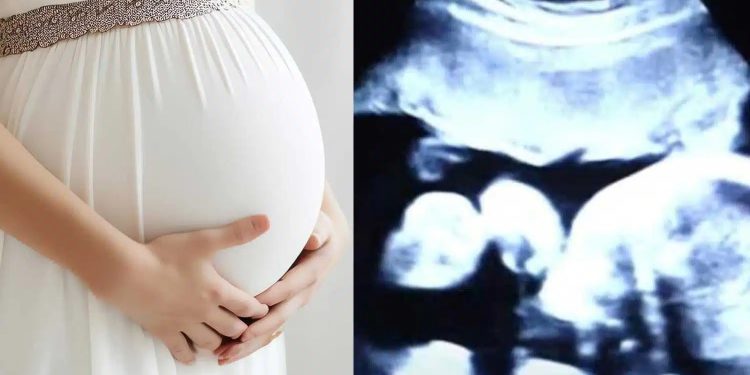

Μια 52χρονη προσφέρθηκε να γίνει παρένθετη μητέρα. Με την βοήθεια της εξωσωματικής γονιμοποίησης, έμεινε έγκυος όχι σε ένα, αλλά σε δύο μωρά!

Έκανε καθημερινά ενέσεις ορμονών και εβδομαδιαίους υπερήχους. Στα μισά της εγκυμοσύνης, η 52χρονη άρχισε να παρατηρεί αιμορραγίες. Φοβήθηκε ότι θα απέβαλε, αλλά οι γιατροί την διαβεβαίωσαν ότι όλα ήταν εντάξει.

Μετά από 37 εβδομάδες, ήρθε η ώρα να γεννηθούν τα μωρά, αλλά με κάποια μικρά απρόοπτα, όπως θα δείτε στο παρακάτω βίντεο.